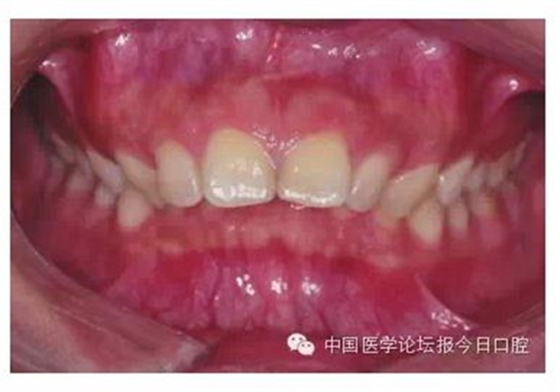

此外,對(duì)于牙冠明顯舌傾容易形成骨皮質(zhì)支抗而不利于牙齒遠(yuǎn)中移動(dòng)的病例,我們可以考慮選擇正轉(zhuǎn)矩度的尖牙托槽(圖1)。

圖1 牙冠明顯舌傾,容易形成骨皮質(zhì)支抗者,可考慮選擇正轉(zhuǎn)矩度的尖牙托槽